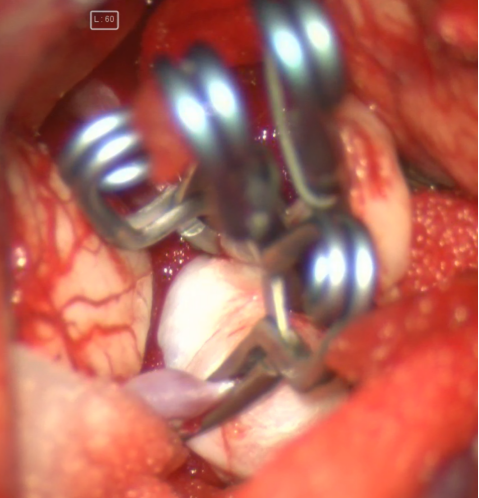

术中电生理未见明显异常,因此未进行进一步血流重建处理。